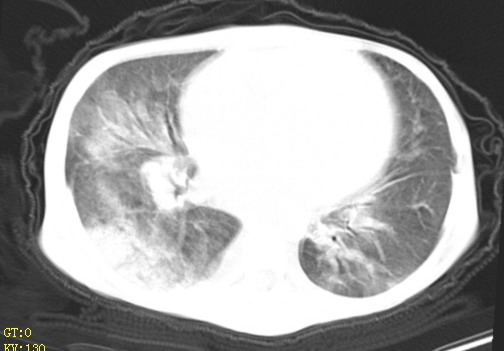

女,12岁,气促、咳嗽2天,3个月前查胸片示:两肺感染,急诊入院查ct,血常规等未检查。

双肺中下野不规则片絮状阴影,中外带明显,双侧胸腔少量积液,心影增大,心腔密度减低,隆突下及左侧气管旁见钙化淋巴结影,考虑双肺感染、心衰;建议结合临床除外h1n1并急性心衰,先心不能排除。

两肺多发片絮状模糊影,以下肺外带居多,内见支气管气像,纵膈窗未减影,两侧胸腔积液,心影增大,结合心超,支持重症肺炎,非常时期,甲型h1n1流感不排除。